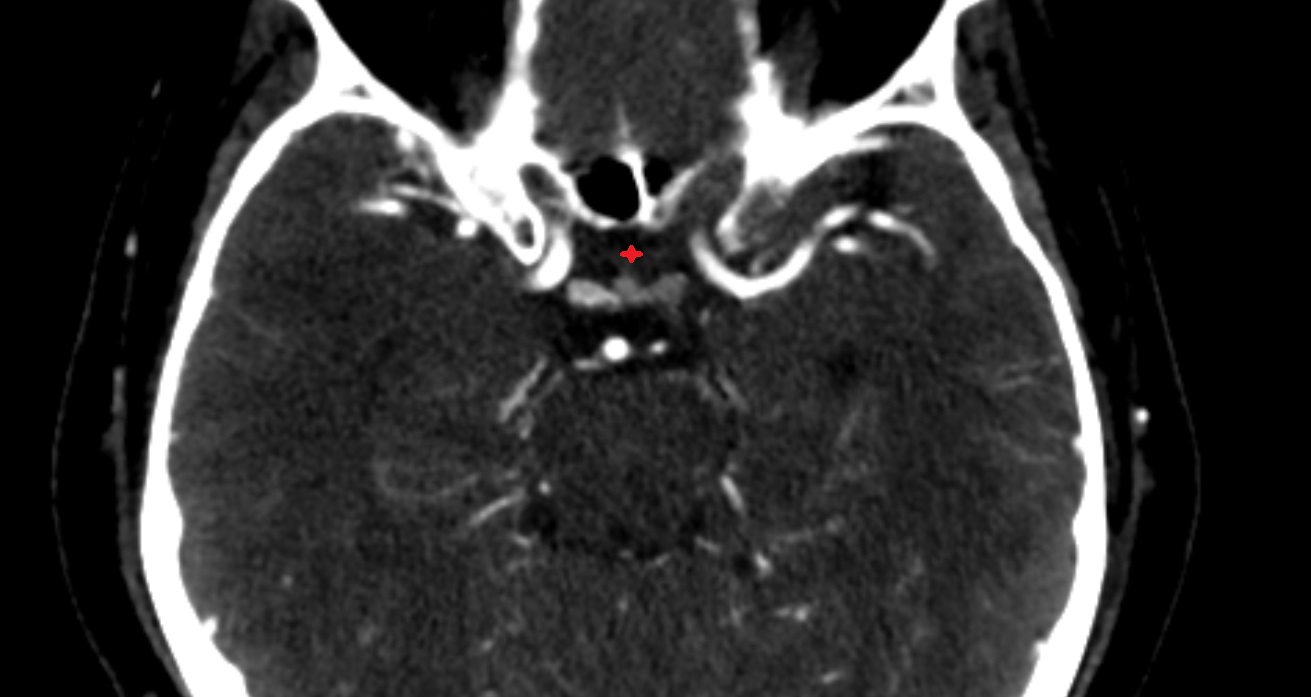

- Interpeduncular Cistern

- Interpeduncular fossa

- Prepontine cistern